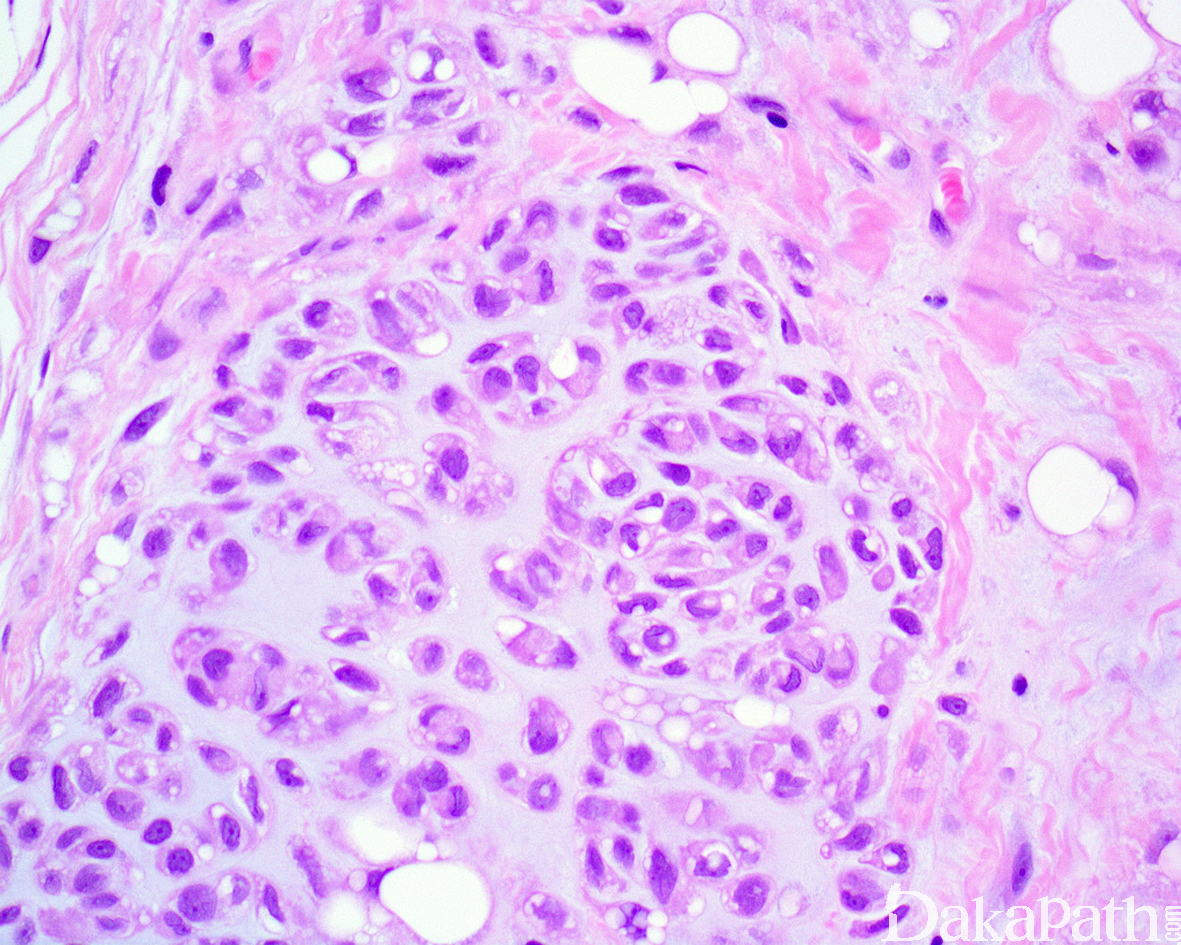

镜下肿瘤边界清楚,由薄的纤维性间质分隔呈小叶状;

小叶由位于软骨黏液样基质内的片状、巢状或索状圆细胞以及数量不等的成熟脂肪细胞组成;

圆细胞胞浆空泡状或嗜酸性颗粒状,有时可见多个空泡形成并挤压核形成核切迹从而类似于脂肪母细胞;

瘤细胞核卵圆形或肾形,核染色质均匀细腻,核仁不明显或含小的嗜碱性核仁,无核异型性,核分裂像罕见;

基质呈软骨黏液样或黏液玻璃样变样,围绕嗜酸性或空泡状细胞周围形成类似于软骨的陷窝;

肿瘤内血管丰富(各种口径大小的血管均可见,较小的血管常见血栓形成),常见灶性出血和纤维化,偶见钙化或骨化以及慢性炎细胞浸润。